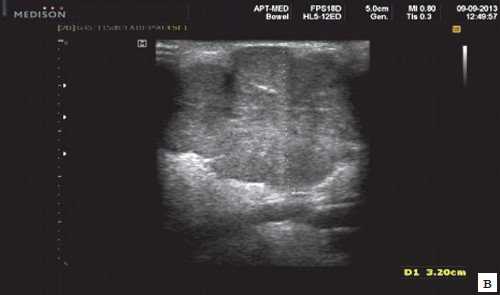

Острый калькулезный сиаладенит. Одностороннее поражение, увеличенная, гипоэхогенная, неоднородная структура железы на УЗИ. Расширение интра- / внегландулярных протоков и слюнной камень. Нет явного увеличения кровоснабжения. Болевая реакция при надавливании датчиком на зону воспаления

Бескаменный сиаладенит. Одностороннее увеличение гипоэхогенной слюнной железы. Нет расширения протока или камней. Болезненность при давлении датчиком. Повышенная внутрижелезистая васкуляризация

Лучший диагностический признак. Острый: одностороннее увеличение, гипоэхогенная структура поднижнечелюстной железы на УЗИ, повышенная васкуляризация при ЦДК ± расширение протока ± слюнной камень. Хронический: одностороннее атрофическое поражение, гипоэхогенная структура, гетерогенные зоны, гиповаскулярный ± расширение протоков ± слюнной камень